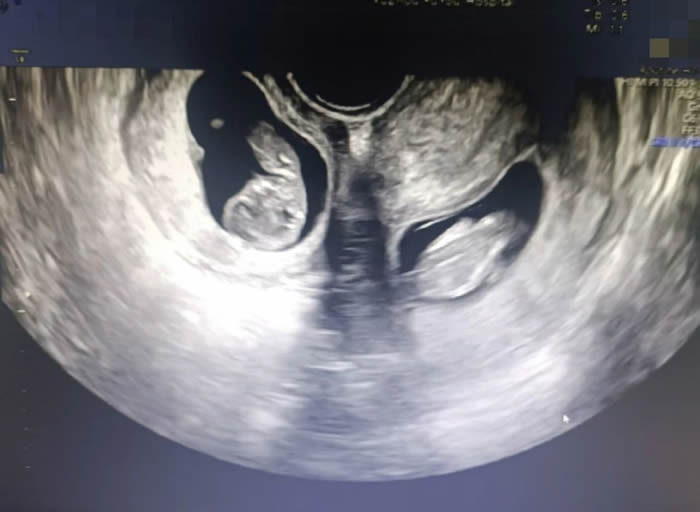

更令人意外的是,早孕期超聲提示,曉曉腹中竟有兩個(gè)胎兒,且兩個(gè)孩子各居“一室”,互不干擾。“在我近30的職業(yè)生涯中,還從未遇到過雙子宮雙胞胎的孕婦。雙子宮女性妊娠風(fēng)險(xiǎn)非常多,很可能會(huì)出現(xiàn)早產(chǎn)、胎兒生長(zhǎng)受限、子宮破裂等情況,每種風(fēng)險(xiǎn)都不容小覷。”產(chǎn)科九病區(qū)主任吳惠瑩如是說。